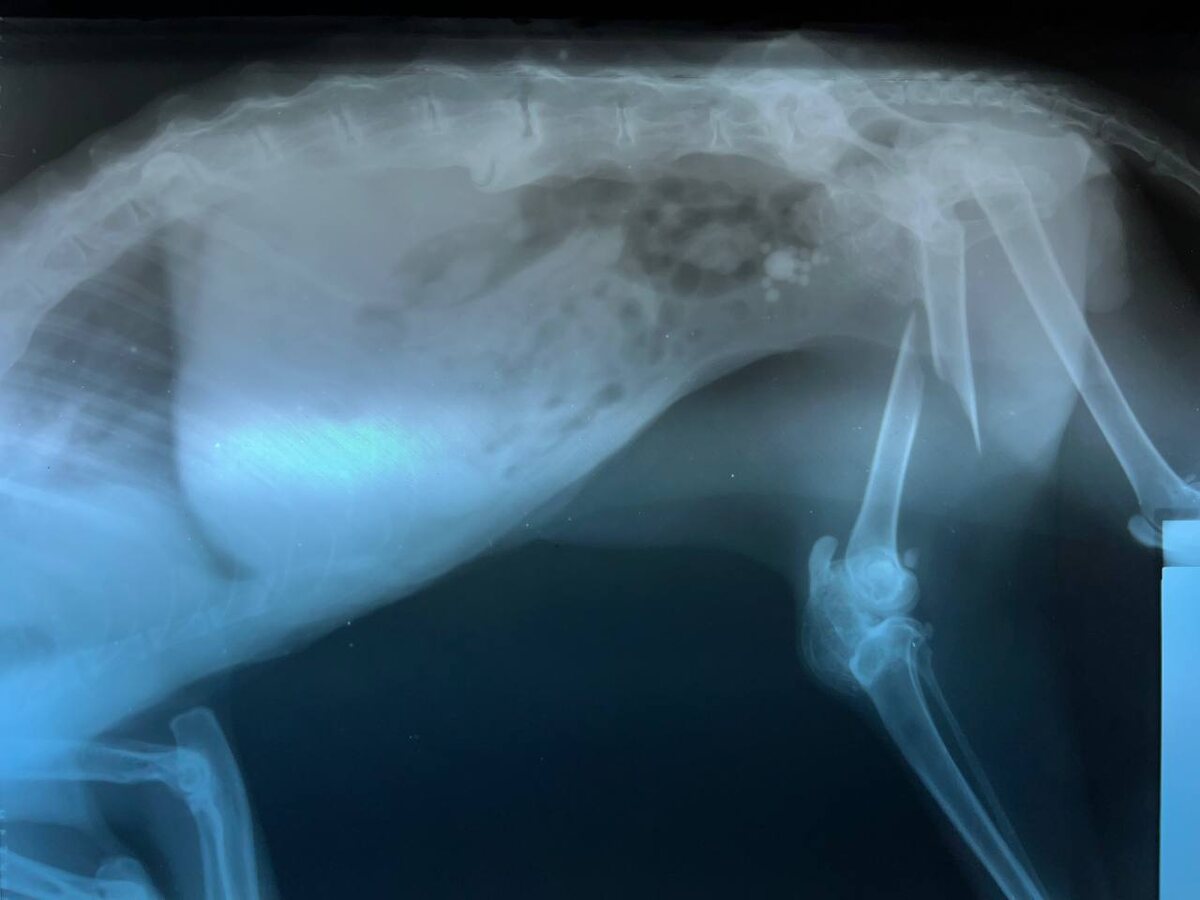

- Рентген – для определения типа перелома.

Переломы у животных — это нарушение целостности кости, которое может произойти из-за травмы, падения, ДТП или на фоне заболеваний (остеопороз, опухоли). Такие повреждения требуют быстрой диагностики и правильного лечения, чтобы избежать осложнений.